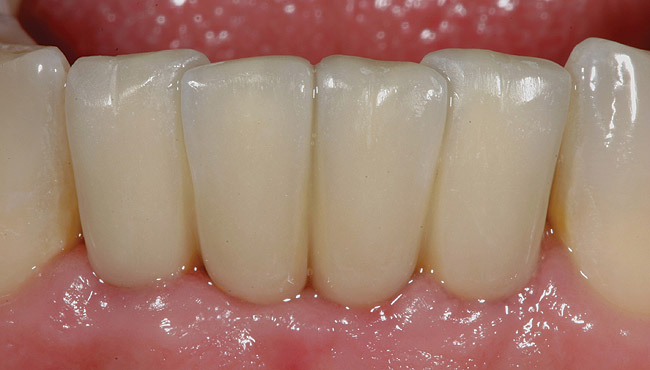

The patient was given postoperative instructions and advised to maintain a soft diet for 6 to 8 weeks to protect the implants. The patient was followed weekly for the first 3 weeks and monthly thereafter. After 4 months of healing, the provisional restoration was removed and the soft tissues were examined. Mature, keratinized gingival tissues were present facially, lingually, and interproximally. Non-keratinized tissue could be seen at the tissue surfaces of the ovate pontics and in the intrasulcular regions of the implant abutment units. No clinical probing depths beyond 1 mm were found adjacent to the abutments. The healed tissue represented an acceptable clinical result especially in light of the gap that had been present at the time of implant placement (Figure 9 and Figure 10). Final impressions were made, and the permanent ceramo-metal screw-retained prosthesis was placed within 8 weeks (Figure 11).

Figure 10  Clinical healing completed.

Figure 10

Figure 11  The final ceramo-metal restoration.

Figure 11